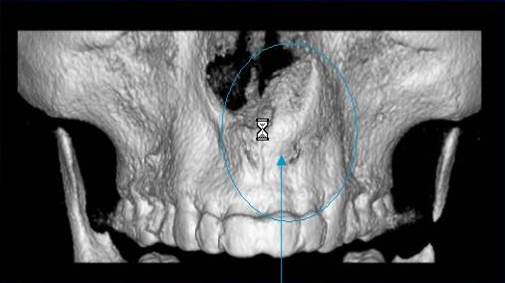

3D DVT - NewTom

Je speciální zubní digitální tříprostorový tomograf (3D), který umožňuje na základě jediného

snímkování vytvořit všechny typy RTG zobrazení, které jsou pro lékaře potřebné. Díky používané technologii tzv. „kuželového paprsku“ a speciálním senzorům je

výrazně zmenšená dávka záření - o více jak 80% proti klasickému CT vyšetření. To je významné zejména u dětí. Pomocí tohoto přístroje je možné zjisti skutečnou situaci v čelistních kostech pacienta tedy množství kosti - můžeme změřit skutečnou šířku i výšku kosti, i kvalitu kosti (hustotu) v místě uvažované implantace. 3D (tříprostorové) zobrazení umožňuje zvýšit prostorovou představu operatéra ještě před vlastní operací a zároveň pacientovi lépe objasnit a ukázat oblast plánovaného zavedení implantátu.

Pacient „neumí číst“ RTG snímky, ale díky 3D zobrazení vidí „svoji skutečnou čelist“

- např. jak je nízká či úzká, vidí průběh nervu nebo velikost čelistní dutiny, což mu umožní i pochopení nutnosti v některých případech provést pomocné zákroky ještě před vlastním zavedením implantátu (viz. kostní štěp, sinus lift, kostní granulát...).

Vyšetření pomocí tohoto přístroje používáme i ve stomatochirurgii (zlomeniny čelistí, zuby moudrosti, cysty, onemocnění čelistního kloubu), ortodoncii (retinované zuby, nadpočetné zuby), parodontologii atd.